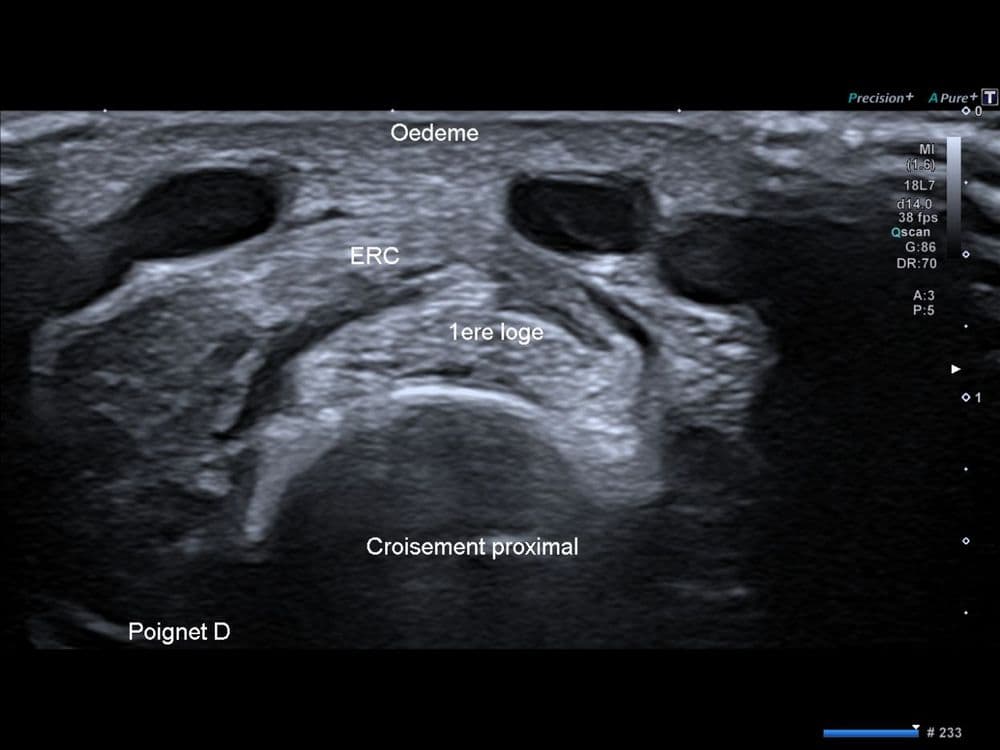

Douleur distal de l'avant-bras chez un jeune patient livreur de course à domicile.

US